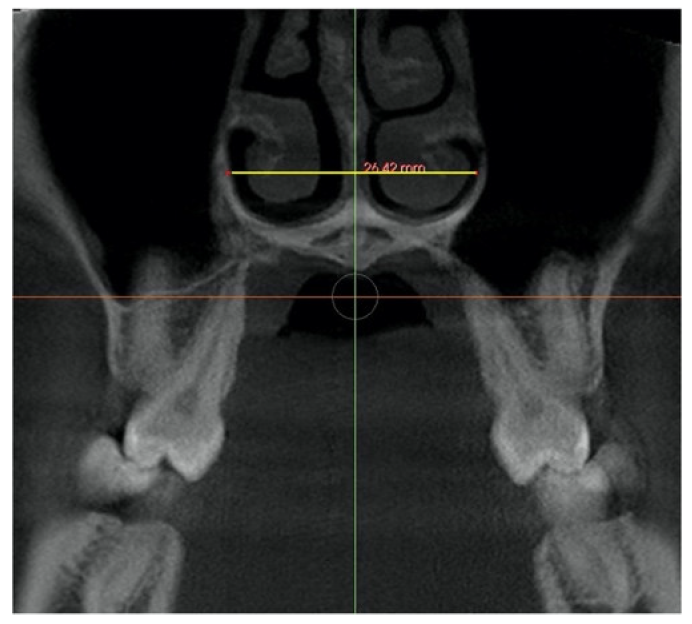

| Nasal Floor (NF) | Distance from right and left external edges of the palatine suture at the level of the nasal floor in the coronal view. On a coronal cross-sectional slice through the center of the first molar. The suture external edges were verified in the axial cross-sectional slice. | ![]() |

| Palatal Floor (PF) | Distance from right and left external edges of the palatine suture at the level of the palatal floor. On a coronal cross-sectional slice through the center of the first molar. The suture external edges were verified in the axial cross-sectional slice. | ![]() |

| Sutural expansion (SEM) | The sutural expansion in the middle of the palate. Distance between the left and right external border of the palatal aspect of the maxilla, in the middle of the palate between the palatine bone and the nasal floor, on a coronal cross-sectional slice at first molar. Through the midportion of the first molar. | ![]() |